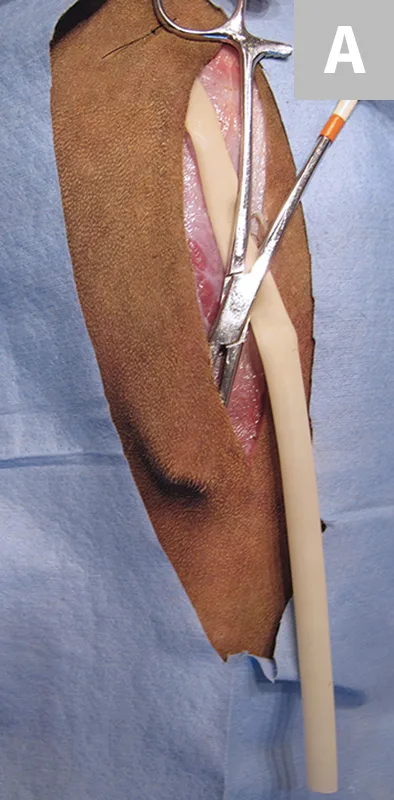

The Jackson-Pratt drainage system is commonly used in veterinary medicine. An alternative is to buy bulk rolls of silicone rubber tubing that can be cut to any length and sterilized. Fenestrations are cut into the distal end of the drain with scissors (Figure 1A); the drain is then attached to a Jackson-Pratt (grenade) reservoir that can be purchased separately. Large syringes can also be used as drainage reservoirs (Figure 1B). An 18-g or larger needle can be used to create a hole(s) along the plunger. The syringe can be attached to the drain. Negative pressure can be established by pulling back on the plunger, and the blunted needle can be placed through the hole(s) in the plunger to maintain the suction. Active drains for small wounds can be made using butterfly catheters and blood collection tubes (Figure 2). The reservoir can be emptied or the blood collection tubes can be replaced when more than half-full to maintain adequate suction. If the reservoir does not have a one-way valve, the tubing can be crimped when emptying it to prevent fluid in the drain tube from flowing retrograde back into the wound. Placement of an active drain after excision of a large intermuscular lipoma in the thigh of a dog is shown in Figure 3.

FIGURE 1 (A) Silicone tubing with multiple fenestrations on the left and a Jackson-Pratt catheter on the right. (B) Reservoir made from 60-cc syringe on the left and a Jackson-Pratt reservoir on the right.

FIGURE 3A

Large intermuscular lipoma being excised from the thigh.